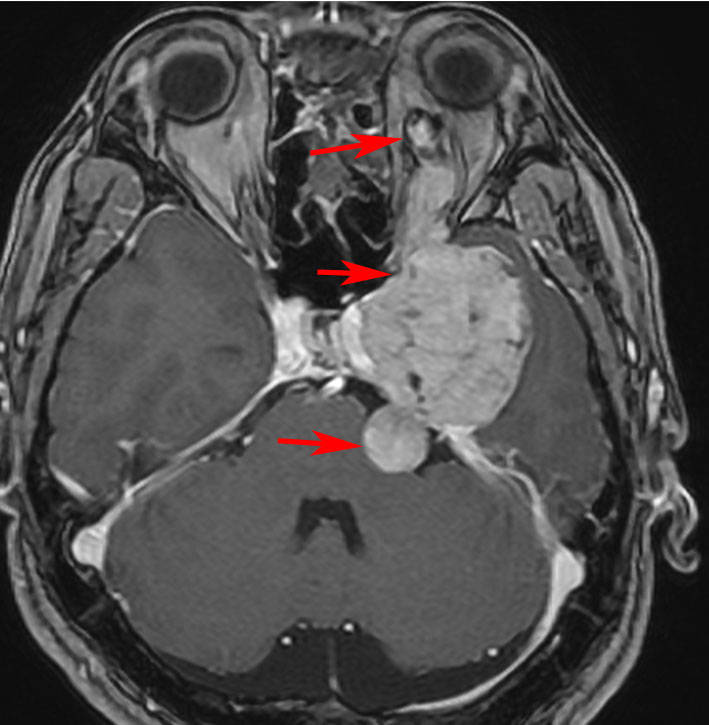

特殊な蔓状三叉神経鞘腫

NF-1ではない孤発例の三叉神経蔦状神経鞘腫です。眼窩内,上眼窩裂,メッケル腔,小脳橋角槽まで伸びる大きなものです。内視鏡の手術はできないので,開頭手術になりますが,全部まとめて摘出できます。